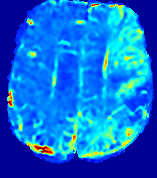

LesionRefer to captionRefer to captionRefer to captionRefer to captionRefer to captionRefer to caption𝐕rgbsubscript𝐕𝑟𝑔𝑏{\bf{V}}_{rgb}Refer to captionRefer to captionRefer to captionRefer to captionRefer to captionRefer to caption𝐕2subscriptnorm𝐕2{\|\bf{V}}\|_{2}Refer to captionRefer to captionRefer to captionRefer to captionRefer to captionRefer to captionRefer to caption3.53.53.52.82.82.82.12.12.11.41.41.40.70.70.70.00.00.0(mm/s)𝑚𝑚𝑠(mm/s)D𝐷DRefer to captionRefer to captionRefer to captionRefer to captionRefer to captionRefer to captionRefer to caption0.0200.0200.0200.0160.0160.0160.0120.0120.0120.0080.0080.0080.0040.0040.0040.0000.0000.000(mm2/s)𝑚superscript𝑚2𝑠(mm^{2}/s)Slice #1Slice #2Slice #3Slice #4Slice #5Slice #6

Figure 3: PIANO feature maps for one stroke patient, where the lesion is located in the left hemisphere. Top row: segmented stroke lesion region (white) on different slices, obtained from ISLES 2017. The corresponding slices for the PIANO feature maps are shown in the following rows.

For a better insight into an estimated velocity field 𝐕𝐕{\bf{V}} and diffusion field 𝐃𝐃{\bf{D}}, we compute the following maps: (1) 𝐕rgbsubscript𝐕𝑟𝑔𝑏{\bf{V}}_{rgb}: Color-coded orientation map of 𝐕=(Vx,Vy,Vz)T𝐕superscriptsuperscript𝑉𝑥superscript𝑉𝑦superscript𝑉𝑧𝑇{\bf{V}}=(V^{x},V^{y},V^{z})^{T}, obtained by normalizing 𝐕𝐕{\bf{V}} to unit length and mapping its 3 components to red, green, blue respectively; (2) 𝐕2subscriptnorm𝐕2\|{\bf{V}}\|_{2}: 222 norm of 𝐕𝐕{\bf{V}}; (3) D𝐷D: scalar field in Eq. 5.

Fig. 3 and Fig. 4 show the PIANO feature maps estimated from two ISLES 2017 patients: all are highly consistent with the lesion in both cases. Details of the blood flow trajectories are revealed in 𝐕rgbsubscript𝐕𝑟𝑔𝑏{\bf{V}}_{rgb} by the ridged patterns and the sharp changes of colors in the unaffected (right) hemisphere, while the flat patterns appearing within the lesion provide little directional information about the velocity and indicate low velocity magnitudes. Velocity magnitudes are more directly visualized via 𝐕2subscriptnorm𝐕2\|{\bf{V}}\|_{2}, from which one can easily locate the lesion where 𝐕2subscriptnorm𝐕2\|{\bf{V}}\|_{2} is low. D𝐷D also indicates lower diffusion values in the lesion, though with less contrast potentially due to the fact that it captures the accumulated effect of CA diffusion at the voxel-level.